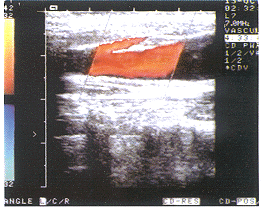

患者男,11岁。无意中发现右侧颈部屏气后隆起而来诊。体检:患儿屏气后可见右侧颈部局部隆起,触之柔软、囊性感,未触及搏动及震颤,临床诊断:右侧颈内静脉扩张。彩超检查:右侧颈内静脉局部呈梭形扩张,扩张段长约30mm,扩张内径:平静呼吸为14.5 mm,屏气后为19.7 mm,其扩张段静脉内可见一带状强回声分隔(图1),将扩张段分为内外两个管腔,分隔长约36mm,一端游离(图2)。CDFI:内外两个管腔血流速度不同,内侧快于外侧。左侧颈总静脉内径:平静呼吸为7.2mm,屏气后为9.3 mm,血流未见异常。彩超诊断:右侧颈内静脉扩张并重复畸形,左侧颈部静脉未见异常。行阔筋膜扩张静脉包裹术,术中见颈内静脉被分隔为内外两个管腔,屏气后两个管腔均扩张。

图1 箭头所示处为颈内静脉分隔